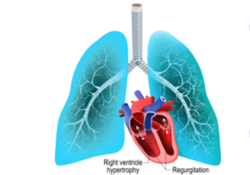

Un certain nombre de maladies peuvent entraîner le rétrécissement, la rigidité ou l’obstruction des vaisseaux sanguins. Le débit du sang du cœur vers les poumons diminue, ce qui oblige le ventricule droit (cavité du cœur qui propulse le sang vers les poumons) à fournir un plus grand effort. Cet effort supplémentaire entraîne parfois une augmentation du volume (hypertrophie) du ventricule droit, laquelle peut causer une insuffisance cardiaque.